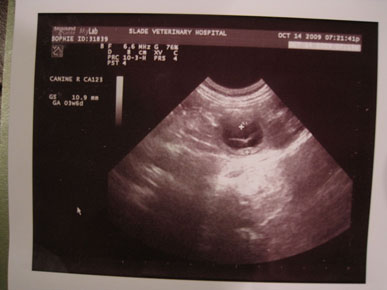

Once upon a time, there was a Princess named Sophie and her Prince Lord Hiawatha. On October 14, 2009, they found out that they were expecting 7 puppies.